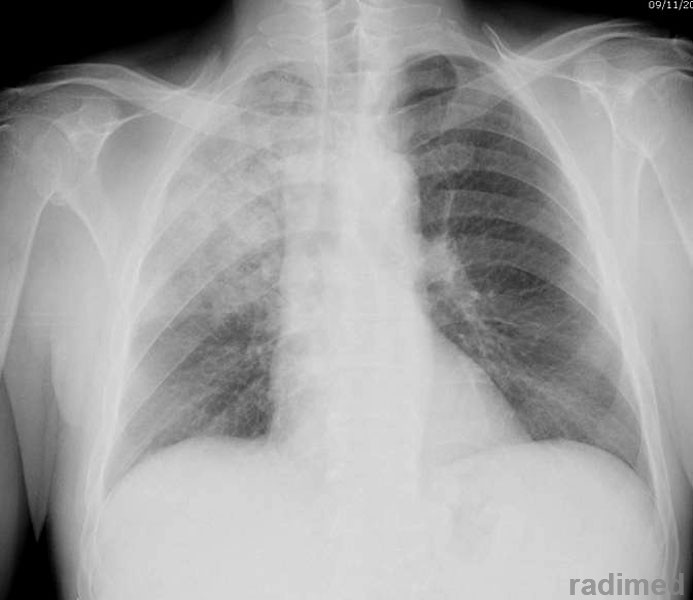

En este ensayo clínico doble ciego de pacientes internados en Cuidados Intensivos y tratados con ventilación mecánica durante al menos 3 días, un ciclo posterior de 3 días de amikacina inhalada redujo la carga de neumonía asociada al ventilador durante 28 días de seguimiento en comparación con el grupo de control. New England Journal of Medicine, 30 de noviembre de 2023.

En los pacientes sometidos a ventilación mecánica durante al menos 3 días, un ciclo posterior de 3 días de amikacina inhalada redujo la carga de neumonía asociada al ventilador durante el seguimiento de 28 días, en comparación con el placebo. New England Journal of Medicine, 25 de octubre de 2023..